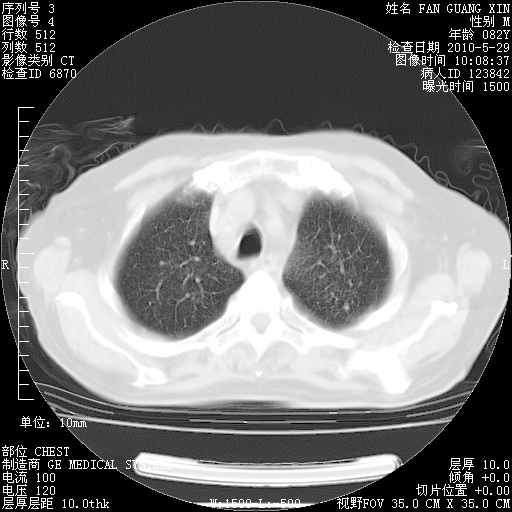

再治疗10天后的肺部CT

再治疗10天后的肺部CT 纵膈窗

肺部体征:呼吸25次/分,心率100次/分,呼吸音增粗。无干湿罗音。

血常规:15.36×10 [sup]9[/sup]/L  N0.92  L0.036  M0.045 ESR 27mm/h。

血生化:白蛋白33.30g/L  球蛋白23.67g/L  CRP 32.82mg/L 肝肾功能正常。电解质正常。

从白细胞总数和中性比例看好像合并感染。肺部纹理好像比上次多,支气管炎?其他感染?

阅读此次胸部CT,肺间质渗出性改变较入院时有吸收。目前从体温、白细胞、中性分叶明显增高,肯定存在细菌感染(发生医院感染哦,若无消化道及泌尿系统等感染的依据,肺部感染可能大)。若你院头孢哌酮舒巴坦钠耐药率较高,同意你的方案,若48小时体温仍高,可考虑使用碳青霉稀类抗菌药物,同时可予超声雾化、注意滴数时加大液体量。白蛋白33.30g/L较低哦,需加强营养等支持治疗。